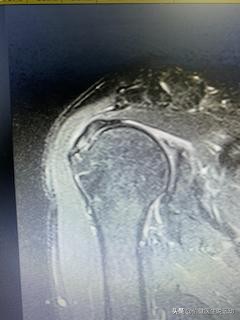

今天就为一位50岁,肩峰撞击综合征三期,有几十年乒乓球球龄的病友做了肩关节镜手术。他也是典型的“游泳肩”,肩峰撞击综合征三期,上面已经谈了,乒乓球和游泳肩部磨损受伤的机制类似。从X光入MR图片可以看出,他是严重的肩锁关节增生,产生肩峰撞击综合征,引起冈上肌及冈下肌磨损。

肩锁关节增生磨损退变

冈上肌腱磨损严重

患者由于频繁的肩部运动导致的损伤,肩锁关节增生磨损退变严重,压迫磨擦冈上肌腱,导致肌腱磨损严重。患者疼痛剧烈,夜间难以入睡,肩关节活动严重受限。